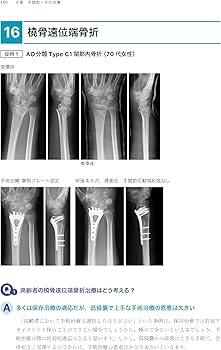

- 著者: 土田芳彦- タイトル: 考える外傷整形外科!- 出版社: 医学書院ご覧いただきありがとうございます。※本商品は裁断されておりますので、「全体的に状態が悪い」としております。※新品をそのまま裁断しているため書き込みはありません。※ ローラー痕や少々のページ折れなどあるかもしれませんが、何卒ご容赦ください。宜しくお願い致します。商品の特性上、返品交換は申し訳ございませんが致しかねますのでご理解宜しくお願い致します。